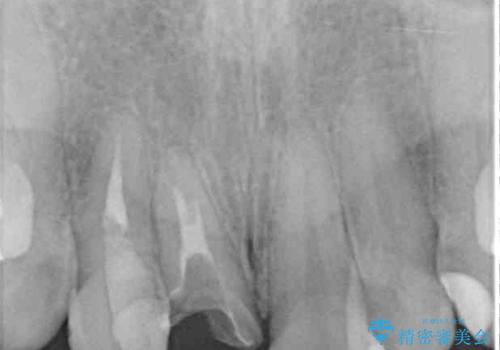

前歯は根管治療が必要であったため、まずは根管治療を行いましたが、痛みが引いた後、矯正治療や前々から治療が必要と言われてきた歯を治療したいとのことでした。

磨きにくく、何度もむし歯治療を繰り返していた前歯をスッキリと整えることができました。